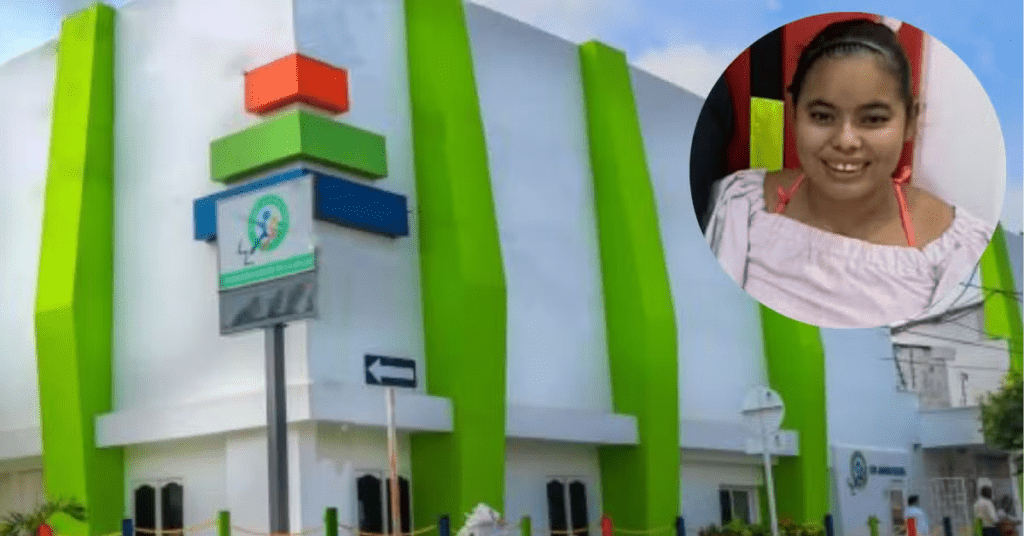

Lo que comenzó como una atención médica terminó convirtiéndose en una historia de abandono que hoy genera rechazo en toda la región. Yoleida Paola Viga Sánchez, una joven de 23 años, permanece desde hace nueve meses en la Clínica Amigos de la Salud, sin que sus familiares vuelvan a hacerse cargo de ella.

La joven ingresó por una infección respiratoria, pero tras su recuperación parcial, nadie regresó por ella. Desde entonces, su caso quedó en un limbo que hoy tiene a la comunidad preguntando: ¿quién responde por su vida?

Yoleida, quien padece epilepsia y presenta un desarrollo cognitivo limitado, requiere acompañamiento permanente. Sin embargo, según denuncias ciudadanas, su familia oriunda de Tierralta no ha asumido responsabilidad, pese a ser plenamente identificada por habitantes del Alto Sinú.